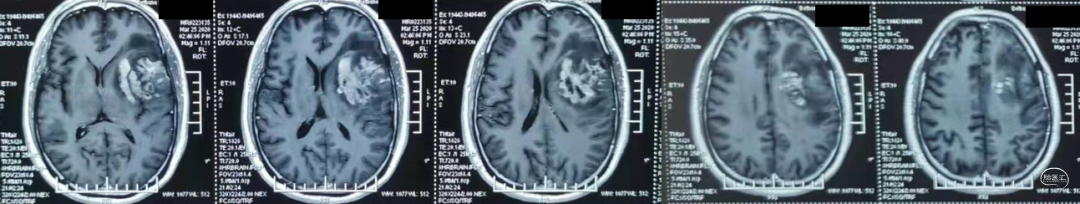

肿瘤电场治疗16天,RT后1月(2020-07-22):图示。

放疗后8月(2021-03-17):如视频和图像。

术后5周开始实施标准的新STUPP方案的辅助治疗,即在同步放化疗后,辅助替莫唑胺化疗的同时使用了电场治疗。目前生存25月,且临床和影像学表现均提示稳定,未见复发迹象。期间,在放疗后7月时复查MRI提示异常FLAIR信号区增大,经我院MDT讨论,考虑到强化信号减轻,无明显占位效应,患者无症状体征,考虑是治疗后水肿,非进展,故继续按原方案治疗。放疗后17月复查MRI出现术区边缘局部强化范围稍增大,但PWI示强化区局部呈低灌注且未见弥散受限表现,MDT讨论考虑为假性进展,继续原方案治疗。后续复查MRI强化范围减轻,证实了MDT的判断证实疾病稳定。患者生存时间已达25个月。全程安全顺利,仅出现一过性轻度皮肤反应。

辅助TMZ治疗过程中每2-3月复查MRI。治疗中曾出现水肿范围增大,尽管有部分区域弥散受限和MRS异常及血流量增加,但是临床症状未加重,仍继续原方案治疗,后续监测PWI显示病变区灌注减低。提示持续肿瘤电场治疗可以使病变长期稳定。此患者每天佩戴肿瘤电场治疗时间接近22小时,中间出现头皮发红和小水泡,经局部外用皮质类固醇和外用抗生素,暂停2天治疗恢复。至今随访25月稳定。说明肿瘤电场治疗联合TMZ治疗较单TMZ治疗明显延长胶质母细胞瘤患者PFS及OS,临床应积极推广使用。